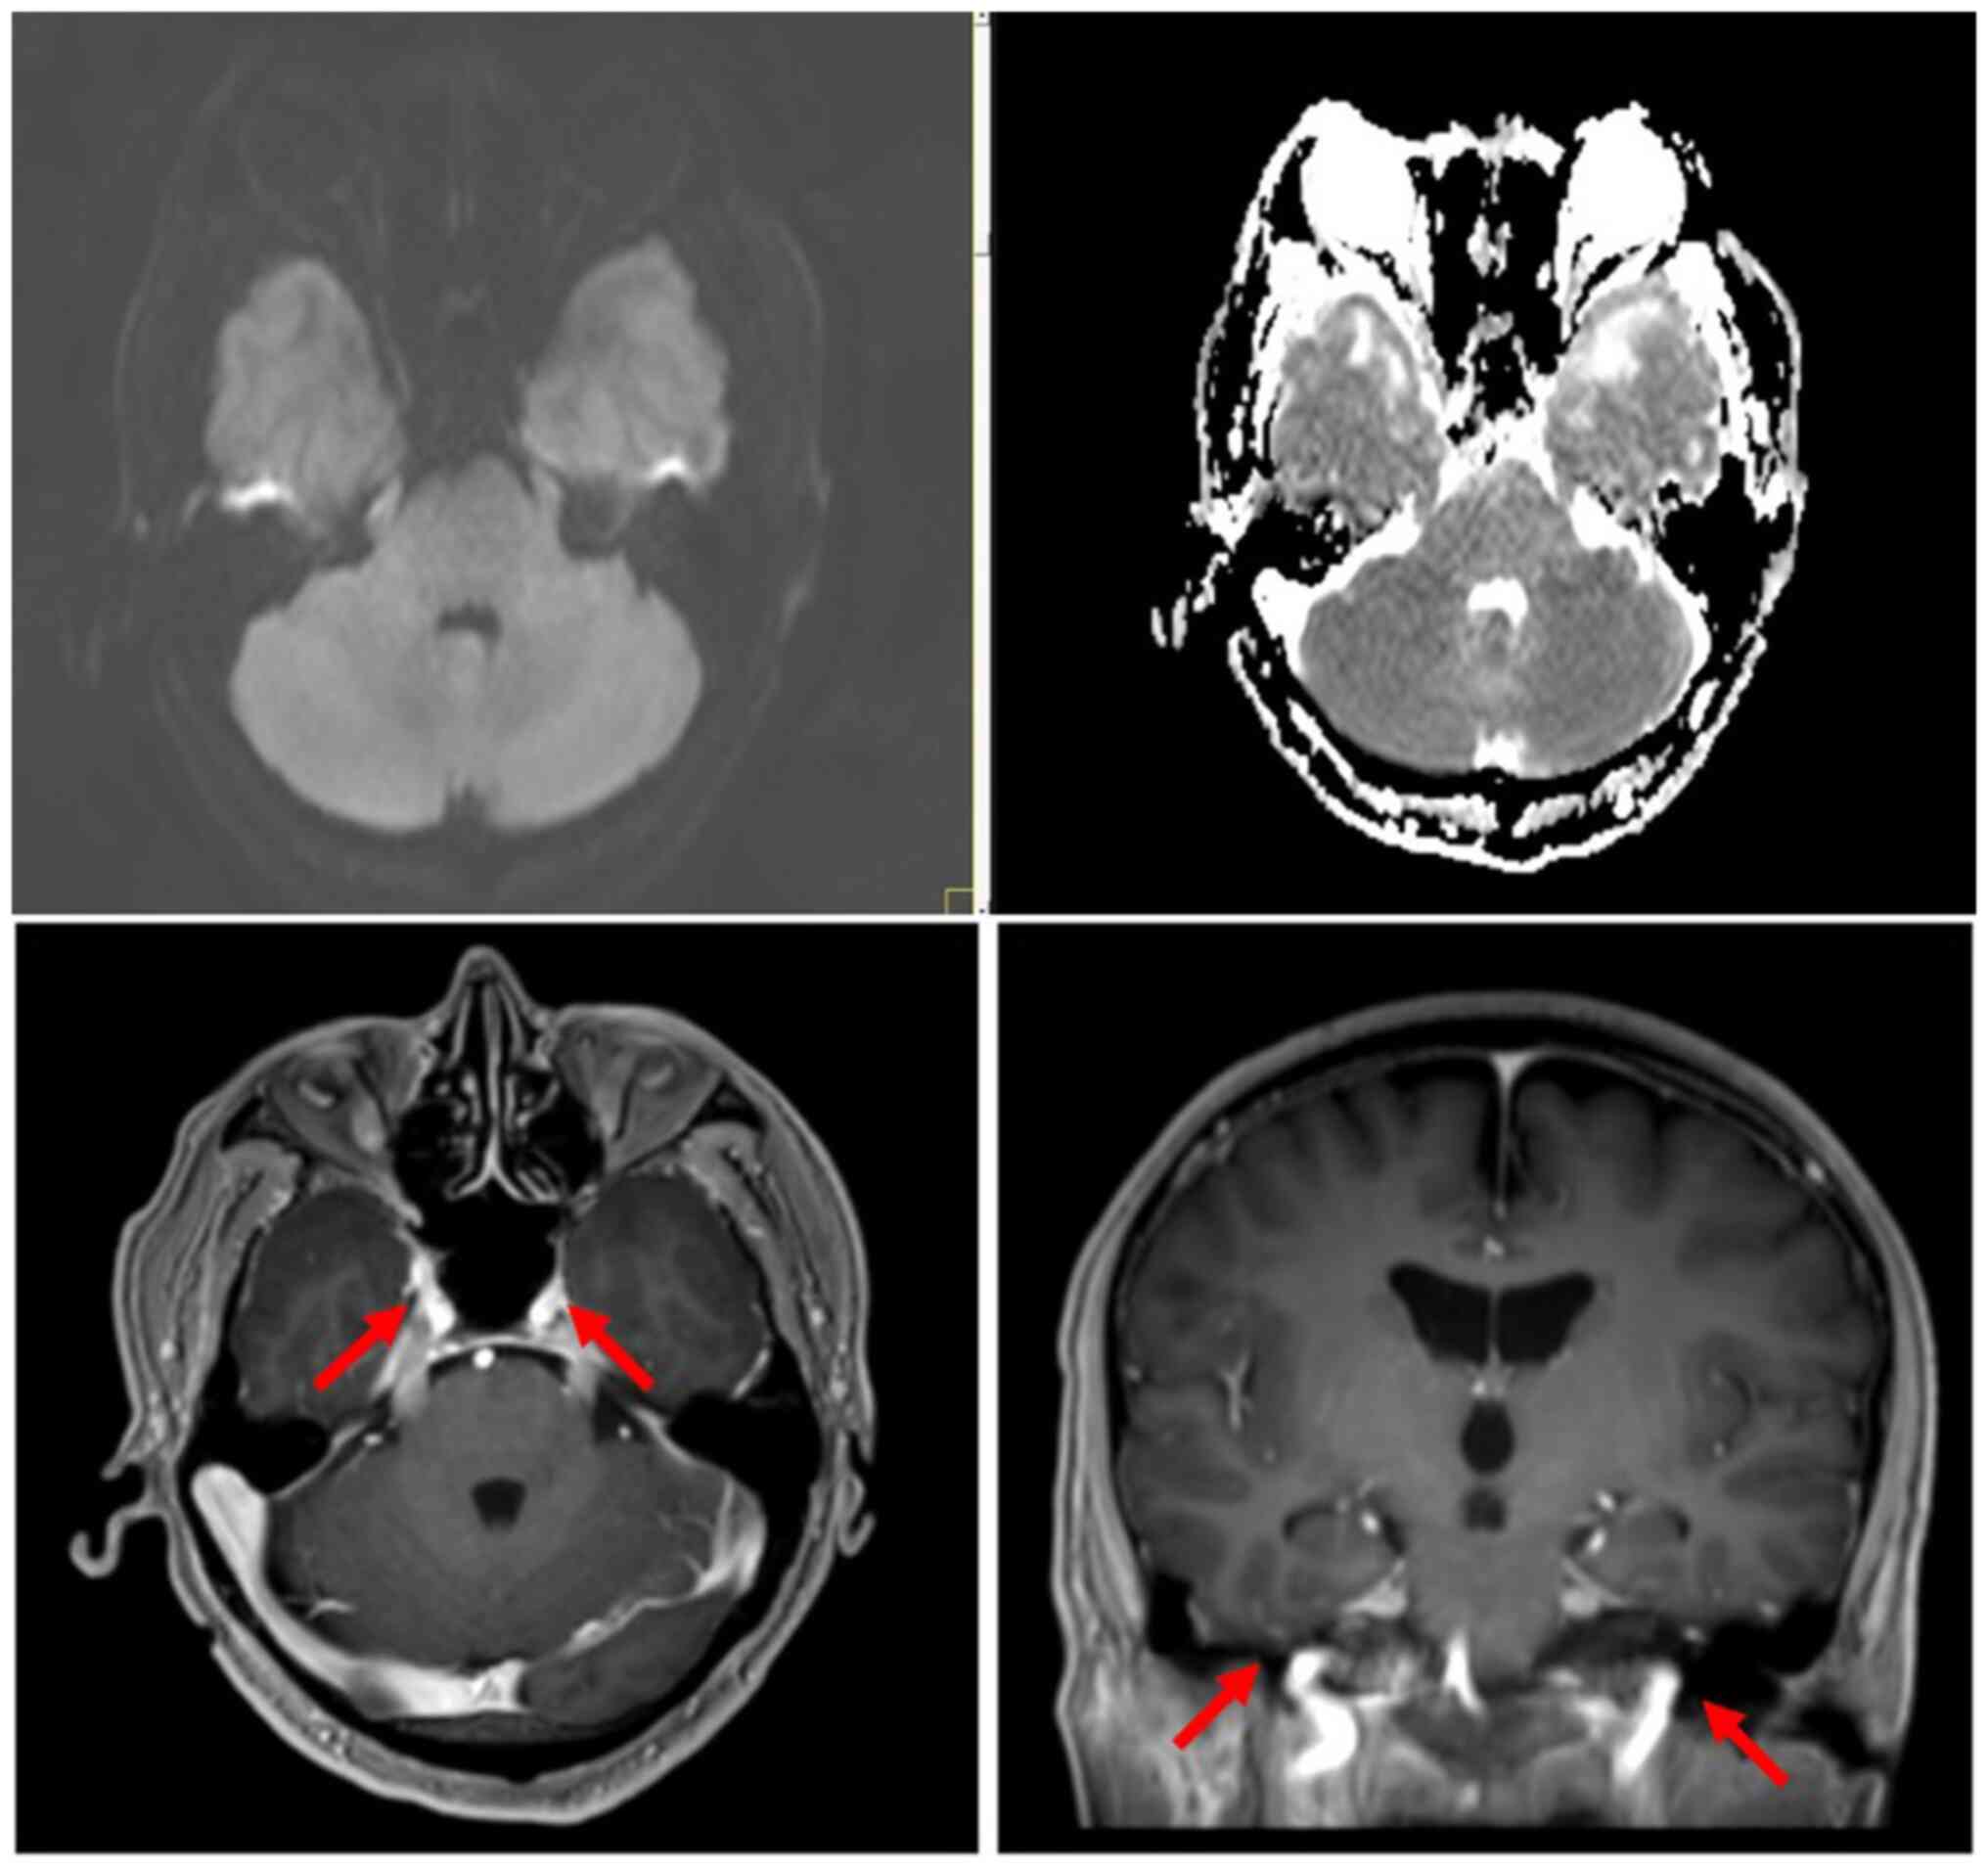

Primary central nervous system (CNS) lymphoma of the meninges is a rare tumor that originates in the meninges and does not show parenchymal or systemic spread. CNS involvement by natural killer (NK)/T‑cell lymphoma accounts for only 2% of all extranodal NK/T‑cell lymphomas, and primary NK/T‑cell lymphoma of the meninges is even rarer. The present study reports a case of a 55‑year‑old male patient with primary NK/T‑cell lymphoma. The patient presented with intermittent dizziness and headaches for the past 1 month prior to presentation. Magnetic resonance imaging of the head identified no overt abnormalities. However, cytological analysis of a Wright‑Giemsa‑stained cerebrospinal fluid (CSF) sample, demonstrated numerous atypical lymphocytes and lymphoma cells. Flow cytometry of the CSF was performed as an auxiliary method, and it showed that a large proportion of the cells in the CSF were of the NK/T‑cell lineage, to indicating a diagnosis of NK/T‑cell lymphoma. Mutations of 14 genes were detected, including JAK3 mutations, upon screening of the CSF for blood system diseases using next‑generation sequencing. Therefore, the present study demonstrated that a CSF cytological examination may be an important component of the diagnostic workup for patients suspected to have a primary meningeal CNS lymphoma.

Figure 1

Figure 2

Figure 3

Figure 4